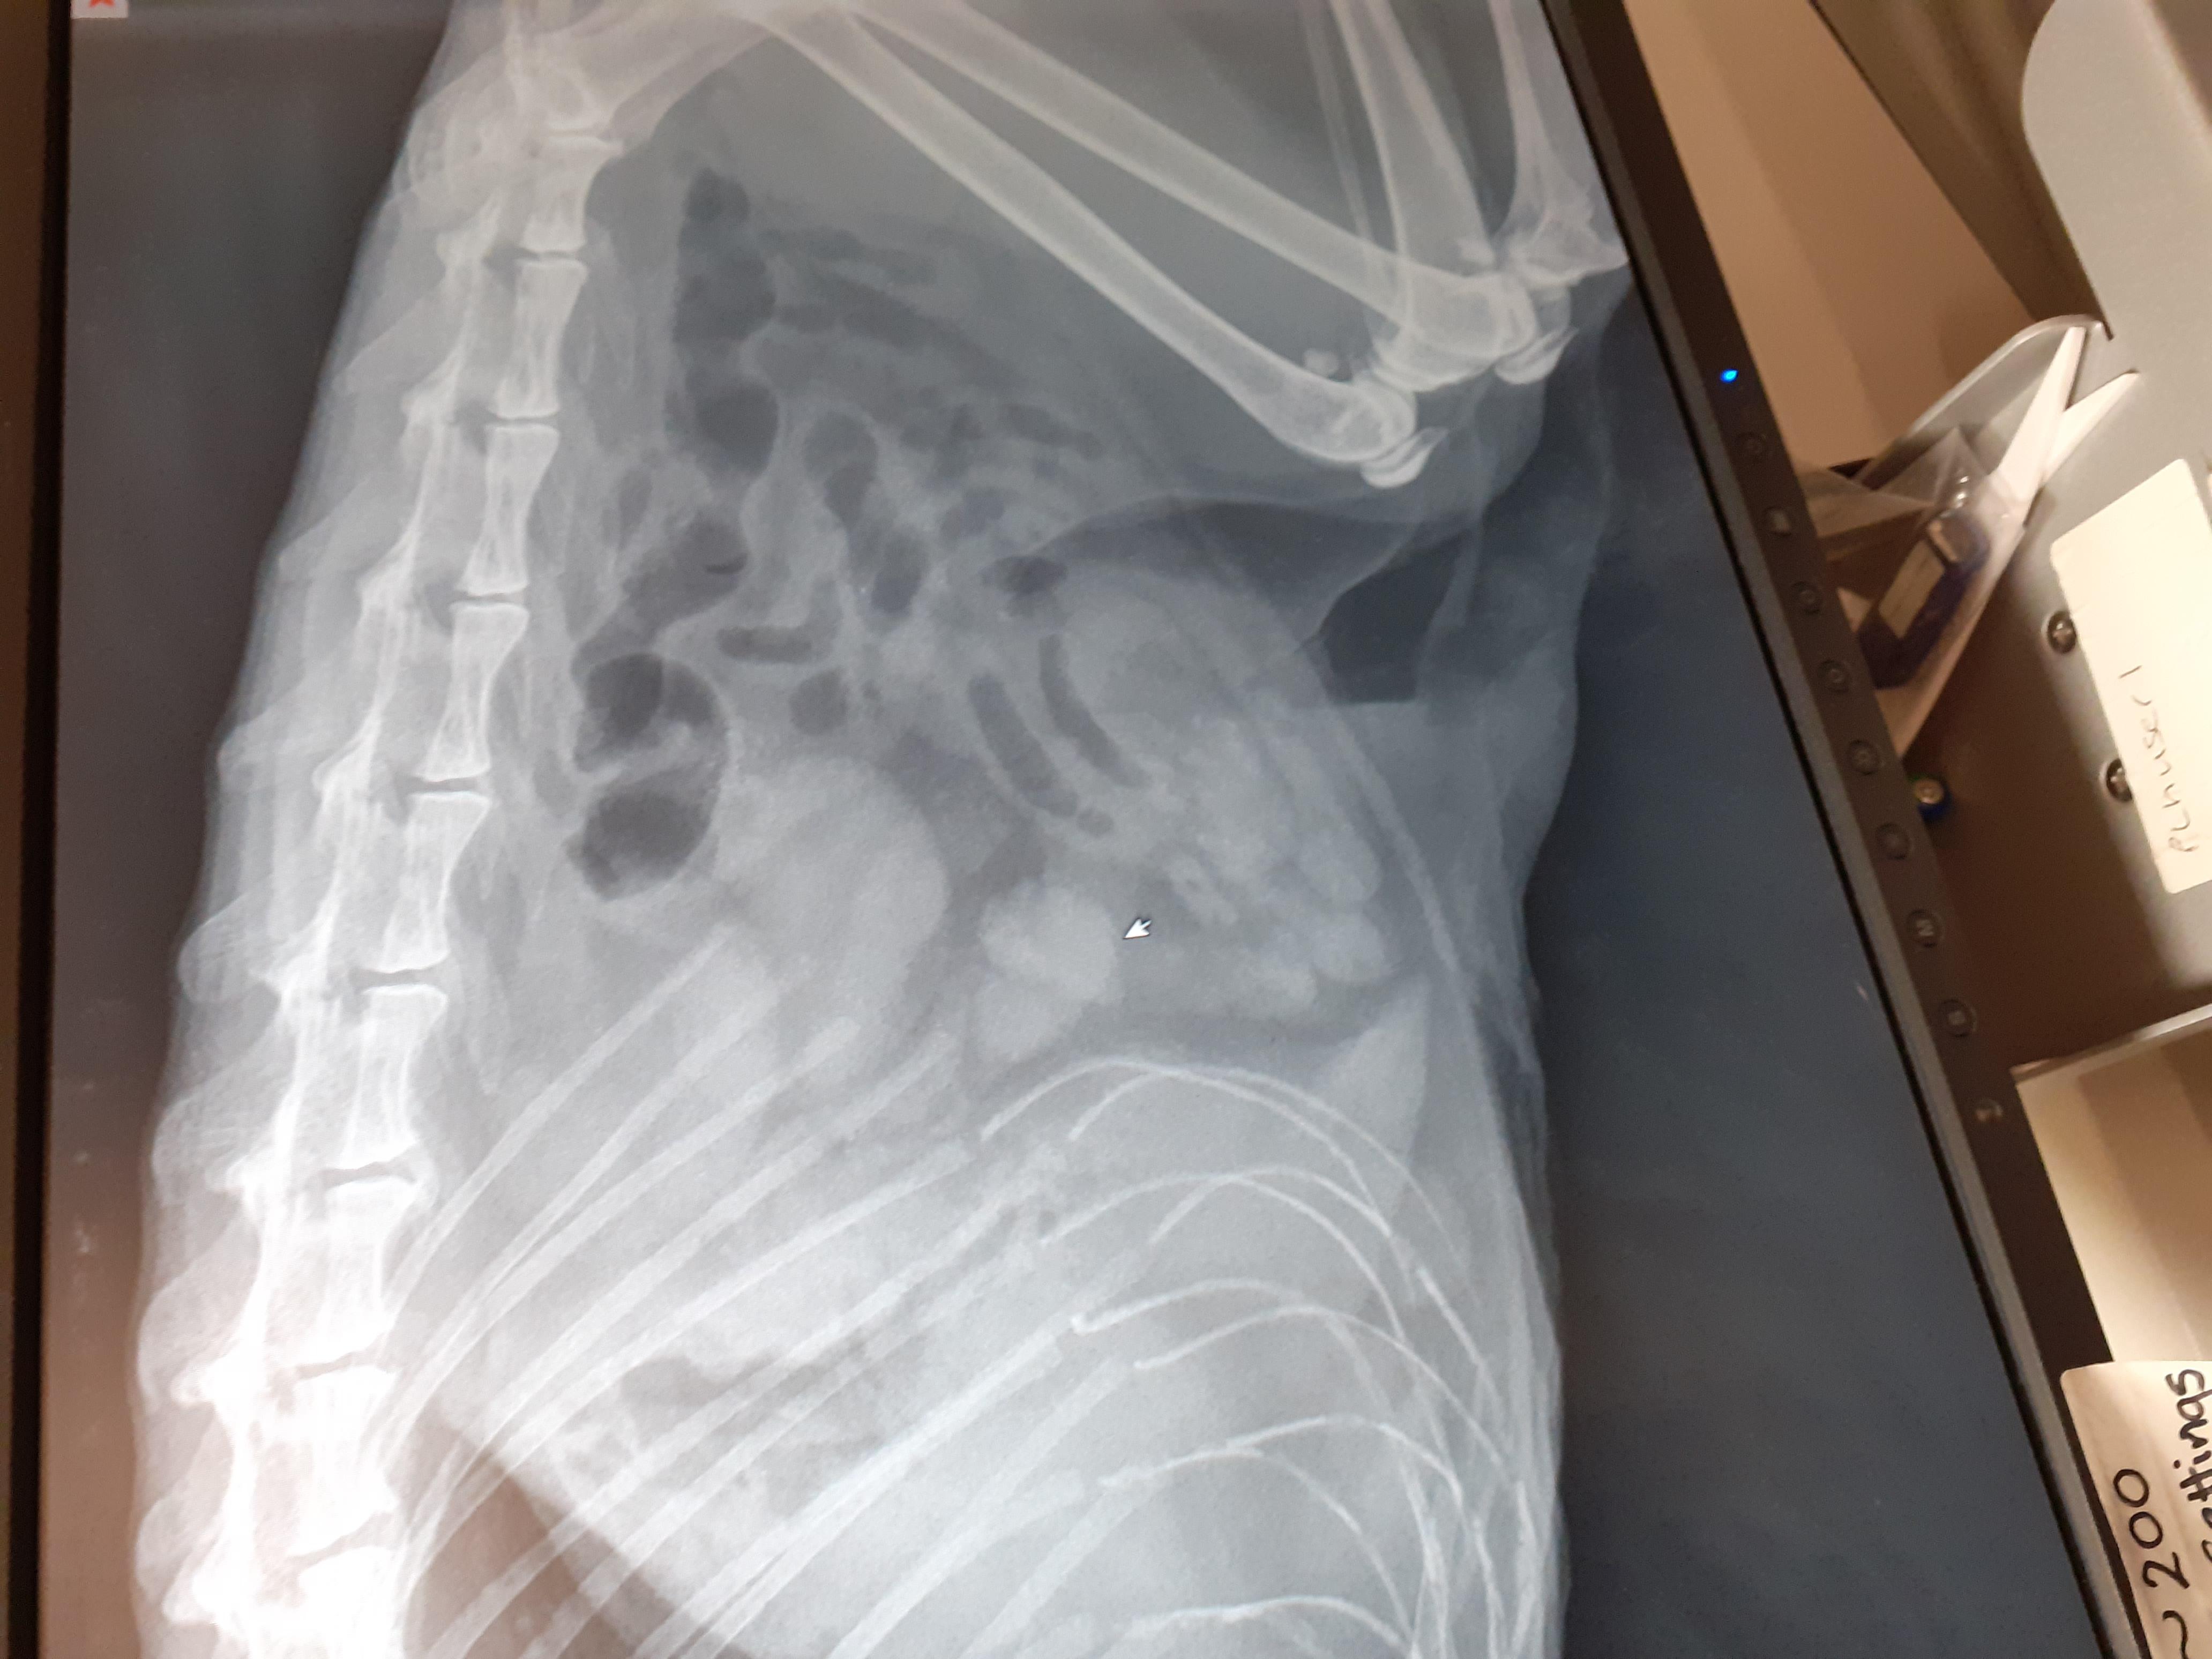

Pet's info: Cat | British Longhair | Female | spayed | 16 years old | 6.3 lbs

Hi I wish to know if the attached xray of my cat shows a tumor in her intestines?

I am so sorry to say but these x-rays are highly suggestive of an intestinal tumor. I would have an ultrasound done next to confirm and then go forward with treatment for suspected intestinal lymphoma, especially if she is symptomatic (i.e. vomiting, decreased appetite, etc). I wish you all the best moving forward with Fluffy. Best wishes and take care.